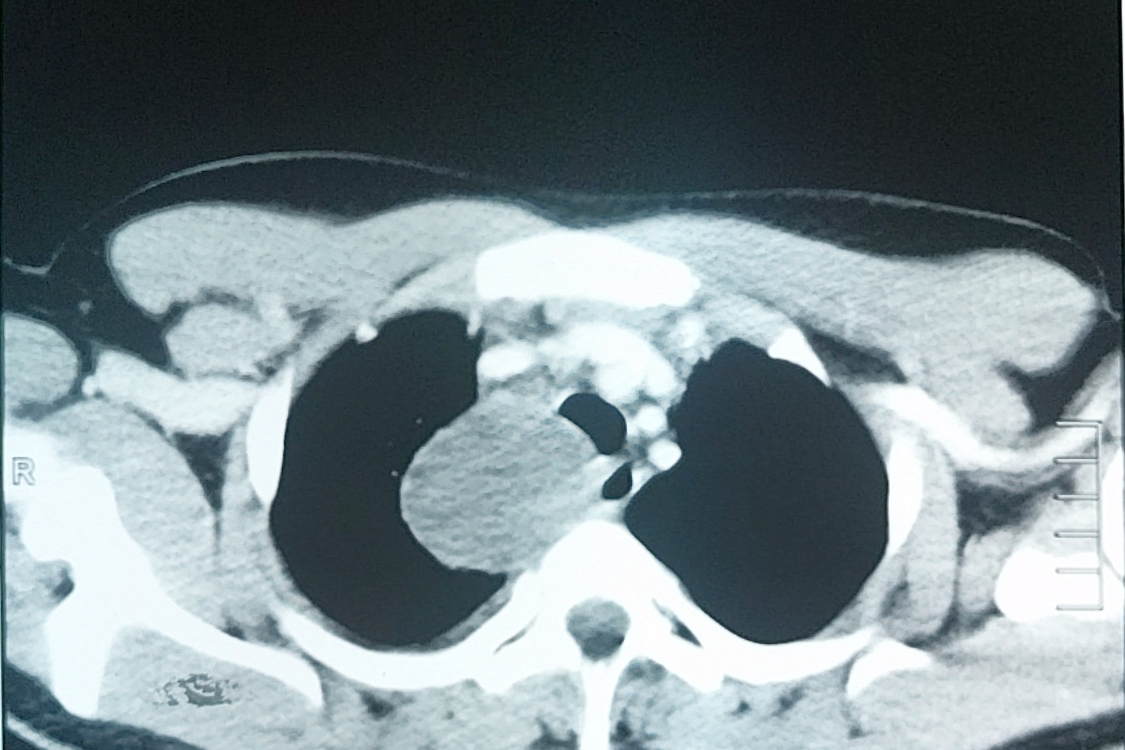

Figure 2. CECT of the chest showing a round homogenous cystic lesion in the right paratracheal region pressing on the esophagus and trachea.

A 16-year-old boy presented with chest pain for the previous seven days that was more on the right side, gradual in onset, dull in character, intermittent, and radiating to the back. It was aggravated on exertion and was relieved with rest. The pain was associated with shortness of breath. The patient also complained of dysphagia, which was occasional and progressive. There was no history of cough or recent chest infection. General physical and systemic examinations were unremarkable. He had a low-grade fever with a hemoglobin of 13.5 g/dl, white cell count of 12.4/dL, and ESR of 52. Other routine lab investigations were within normal limits. His chest x-ray showed a right mediastinal round opacity on the right side of the carina. On his CECT scan Chest, the authors found a well-marginated nonenhancing thick fluid-attenuating lesion centered at the right paratracheal location in the middle and posterior mediastinum on the right side that was pressing on the esophagus and trachea.